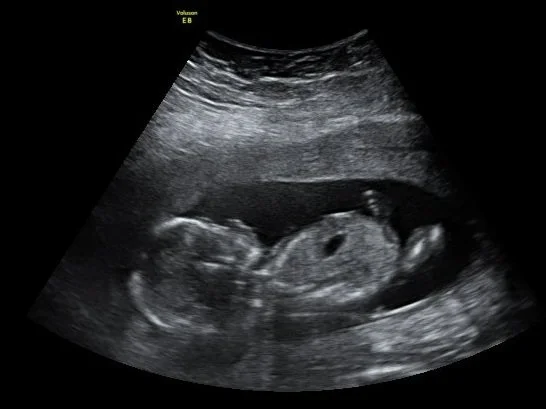

15-20 weeks